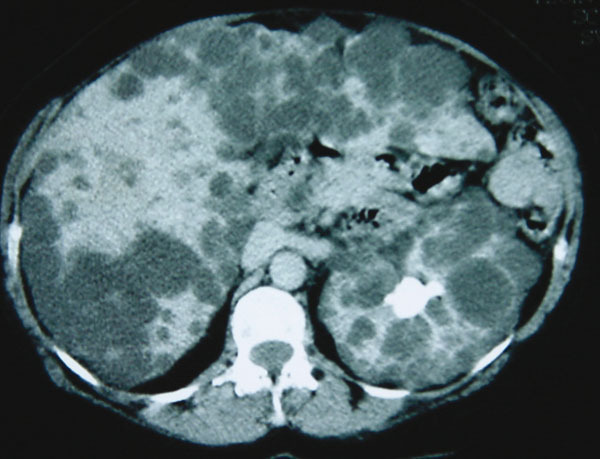

La Revue du Praticien - Jacques Belghiti Lorsqu’il existe plusieurs kystes associés à une maladie polykystique rénale on parle de polykystose hépato rénale.